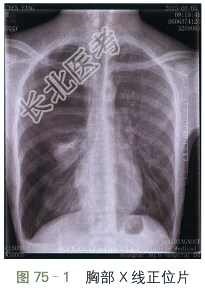

胸部X线正位片(见图75-1)显示右侧肺野大片无纹理透亮区,右侧肋间隙增宽、右侧膈肌低平,纵隔轻度左偏,右侧肋膈角变钝。胸部CT(见图75-2)提示右侧胸腔内大量气体影,右肺压缩不张。

读片分析:本例患者病史为突发右侧胸痛、急性起病。胸部X线正位片和胸部CT扫描提示右侧肺野外中带大片透亮无纹理区,右侧肺门可见压缩不张之肺组织,右侧肋间隙增宽、右侧膈肌低平,纵隔轻度左偏,右侧肋膈角变钝。所有征象均提示大量气胸的诊断。